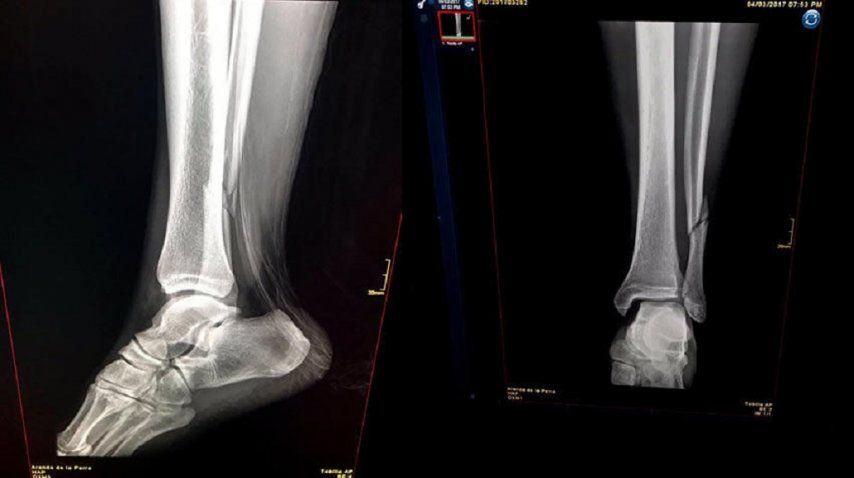

Renato Ibarra, mediocampista de América de México y la selección de Ecuador, sufrió una fractura de peroné durante el partido en el que su equipo enfrentaba al León por el torneo Clausura.

Transcurría el minuto 18 del primer tiempo cuando un golpe del Rifle Andrade le dobló el tobillo izquierdo. El extremo estará entre tres y cuatro meses en rehabilitación por lo que también se perderá partidos con la Selección de Ecuador, en la que ha sido titular durante los últimos meses.